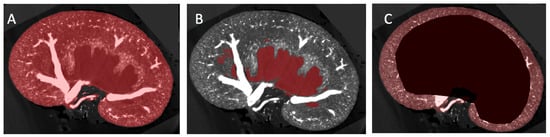

2.2. Image Segmentation and Vascular Density Measurement

3.2. Vascular Modelling of Diabetic Kidney Disease